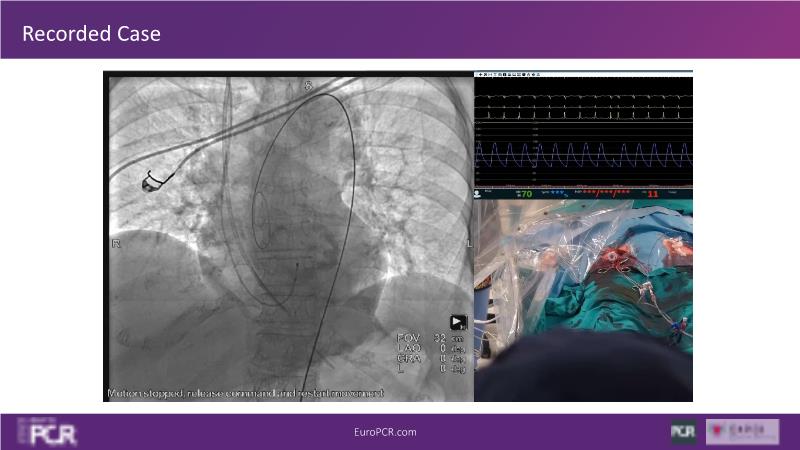

Check out this session if you want to better understand the importance of paravalvular leaks and conduction disorders after TAVI on long-term outcomes. You will also learn about the latest data on the lifetime management of patients with aortic stenosis, and value the importance of TAVI design on durability and TAV-in-TAV options.